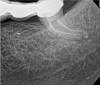

As indicated in Figure 11, the mesial aspect of the distal canal was never touched by instruments, yet he was able to clean, evidenced by the postoperative image. In the past, a case with this level of difficulty would have required at least two appointments, with an interim medication of calcium hydroxide, but the case was treated in a single-visit appointment.  As observed 7 months later (Figure 12), the patient returned completely asymptomatic, and complete bone healing had occurred that exceeded initial expectations.

Fig 11. Case 2: Significant bone loss on the mesial and apical aspect suggested a potential vertical fracture (Fig 9 and Fig 10). Radiographic images were taken immediately postoperatively (Fig 11) and 7 months postoperatively (Fig 12).